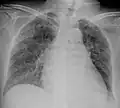

| Chest X ray showing miliary tuberculosis | |

Miliary tuberculosis is a form of tuberculosis that is characterized by a wide dissemination into the human body and by the tiny size of the lesions (1–5 mm). Its name comes from a distinctive pattern seen on a chest radiograph of many tiny spots distributed throughout the lung fields with the appearance similar to millet seeds—thus the term "miliary" tuberculosis. Miliary TB may infect any number of organs, including the lungs, liver, and spleen.[2]

A case of miliary tuberculosis in an 82-year-old woman:

X-ray, 13 days after onset, showing bilateral interstitial infiltrates -

X-ray, 22 days after onset, showing extensive bilateral reticulo-nodular infiltrates -